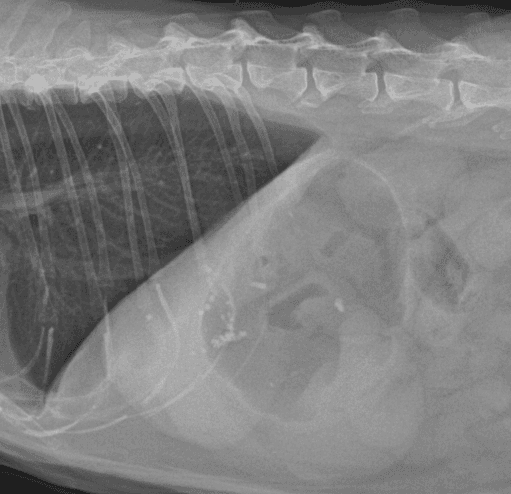

간, 담도 수술은 수술뿐만 아니라, 수술 후 중환자 관리도 중요하기 때문에 외과와 내과의 협진이 매우 중요합니다. 동탄시티동물의료센터에서는 최신 수술 장비의 도입으로 간담도 수술에서 출혈 및 부작용을 최소화 하였으며, 수술 후 협진 시스템을 통해 수술 후 관리에도 최선을 다하고 있습니다.

간종양

최고 사양 영상 장비를 활용한 정밀한 전이 평가

외과 협진 시스템을 통한 신속한 종양 수술

담석

담낭점액종